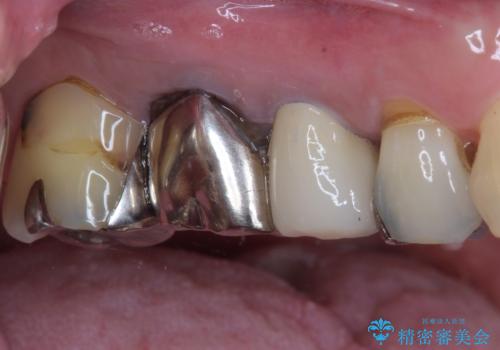

もげてしまった奥歯 オールセラミッククラウンでの補綴治療

- 食事中に歯がもげてしまったとのことで来院された患者様です。

レントゲン写真から、特に大きなむし歯などは認められませんでしたが、根管治療があまり十分に行われているとは言えない状態でした。

まずは仮歯を装着し、根管治療を行った上で土台を植立し、オールセラミッククラウンにて補綴治療を行うこととしました。